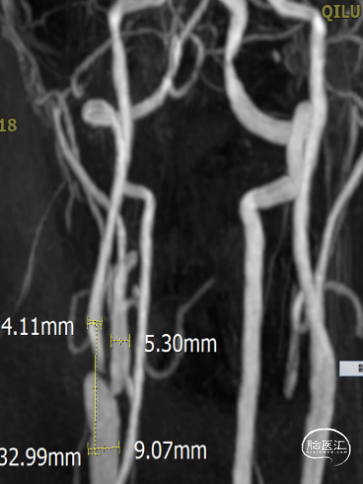

术前评估:术前MRA提示右侧颈动脉起始部重度狭窄大于90%。患者颈总动脉直径9.07mm,颈内动脉直径4.11mm,颈总颈内直径相差较大。

结论:双侧颈动脉硬化并斑块形成,右侧颈内动脉起始段狭窄(狭窄率70-99%)。